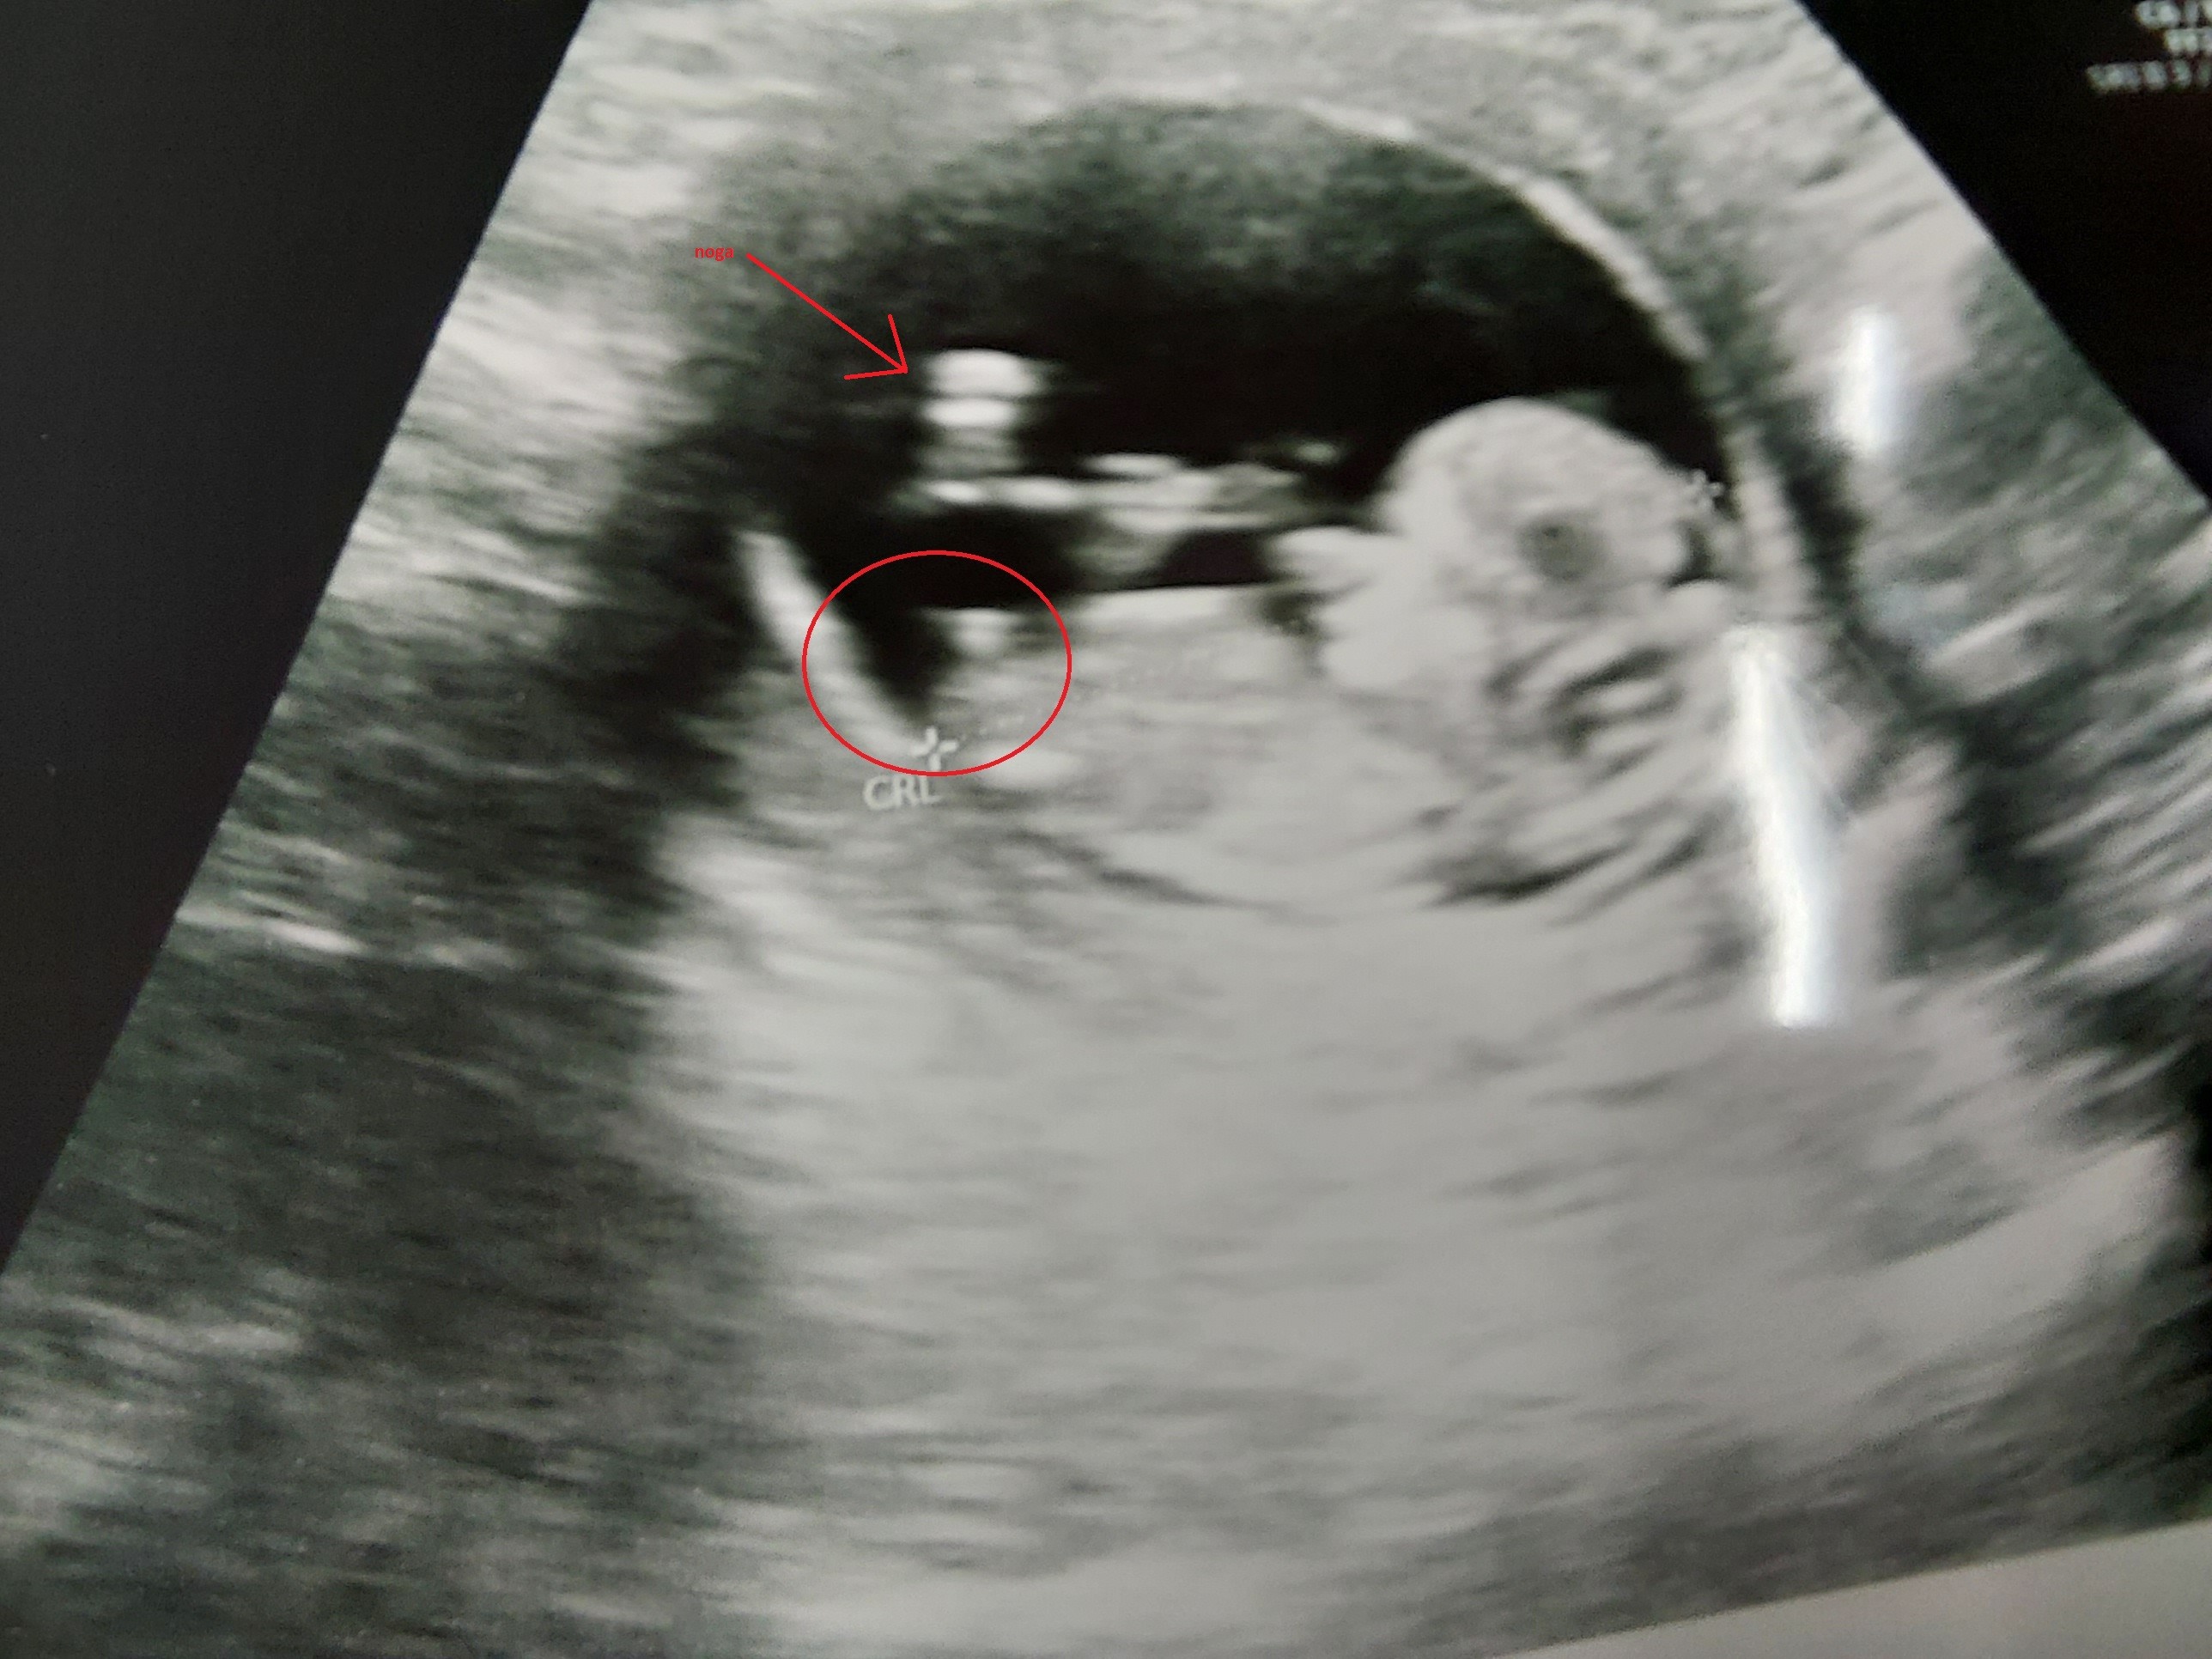

Hej kobietki widać coś waszym zdaniem?

Ja widzę ślicznego dzidziusia😍

A tak na serio to poczekaj do połówkowych. Ja wiem, że chcesz wiedzieć, ale przy tych pierwszych USG o pomyłkę nie trudno.

Lepiej poczekać i mieć pewność, niż się nastawić a potem zawieść.

Poza tym czemu po prostu nie spytałaś lekarza? Wtedy lekarz może spróbować lepiej ustawić zdjęcie. Nie mówiąc już o tym, że 2023 roku bez problemu mamy dostęp do badań nipt i już po 10 tygodniu ciąży w kilka dni ma sę 99,9% pewności co do płci dziecka